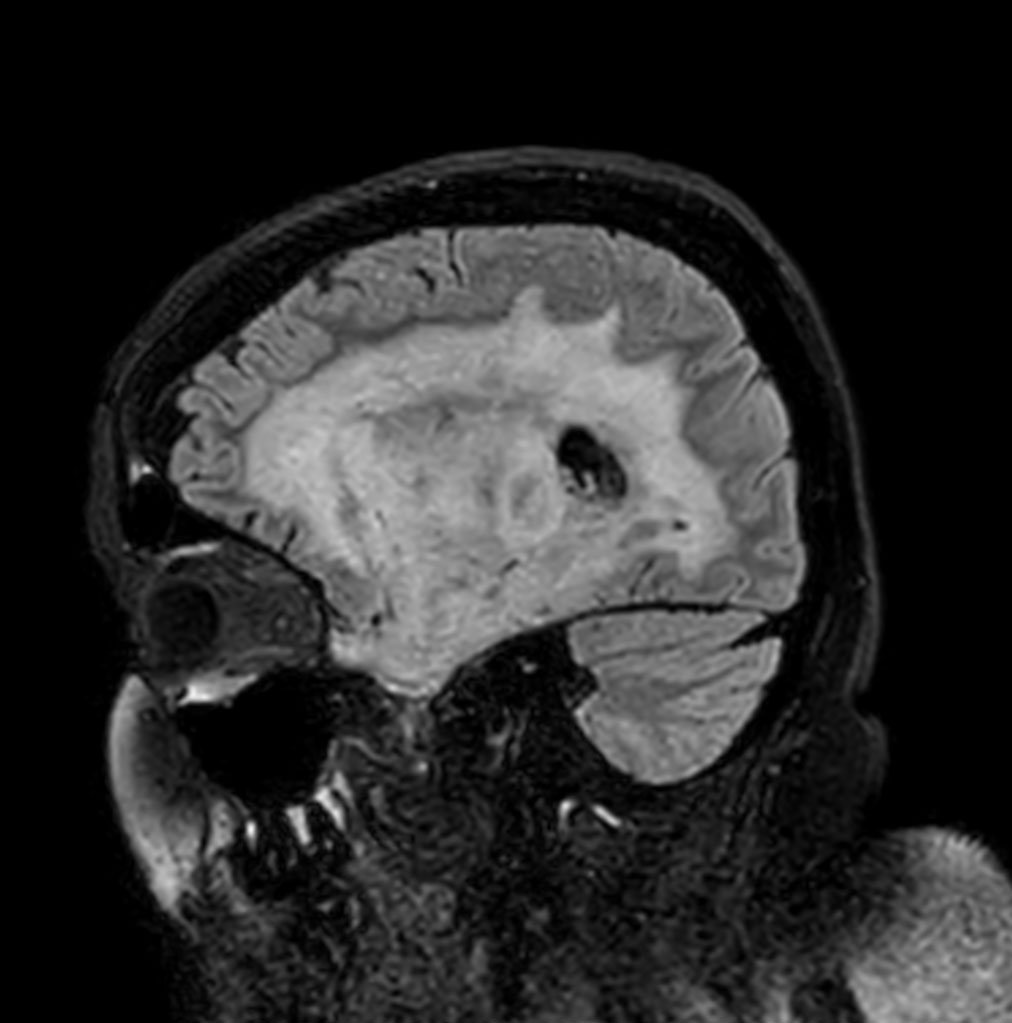

Sagittal 3D BrainVIEW FLAIR

3D BrainVIEW FLAIR (axial reformat)

Patient with a history of astrocytoma. MRI scan requested post radiotherapy treatment. Diagnosis: Recurrent neoplastic disease.